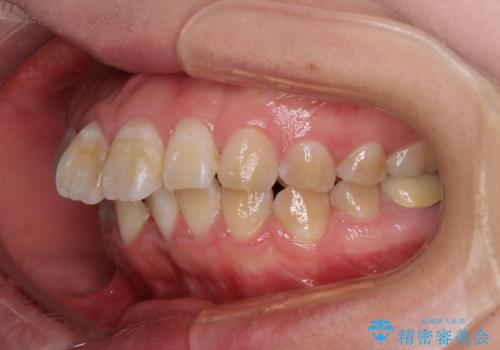

- 口元の閉じにくさと、前歯のでこぼこの歯並びを気にして来院された患者様です。

口元を積極的に引っ込めるために、上下左右の小臼歯計4本を抜歯することとしました。

4本の歯を抜歯したことで、飛び出していた口元が引っ込み、横顔が大きく改善されました。